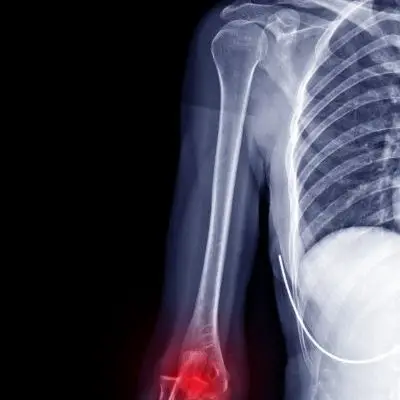

Fractures (Broken Bones)

With 30 bones making up what is generally defined as the arm, wrist and hand there are a vast array of fractures which can occur to this area. Fractures to the forearm are the most common break within the population, with the most of these occur to the distal (hand end) of the radius.

The forearm is made up of two bones: the radius, the bone on the thumb side of the forearm, and the ulna, the bone on little finger side of the forearm. As stated above, the most common arm fracture is in fact a ‘broken wrist’. The break occurs a short distance from the end of the radius and, depending on the mechanism of injury, may even affect the joint as well. Injury will often occur due to a fall onto an outstretched hand and is very common in older individuals as risk of falls increase and bone integrity decreases with osteoporosis.

Though ‘broken wrists’ are common there are a range of other fractures that can affect the arm. These include a break to the middle third of the ulna or radius, fractures of the carpal (wrist) bones or even broken fingers. The most common mechanism for injury is direct trauma to the bone, such as in a motor vehicle accident or collisions in contact sports.